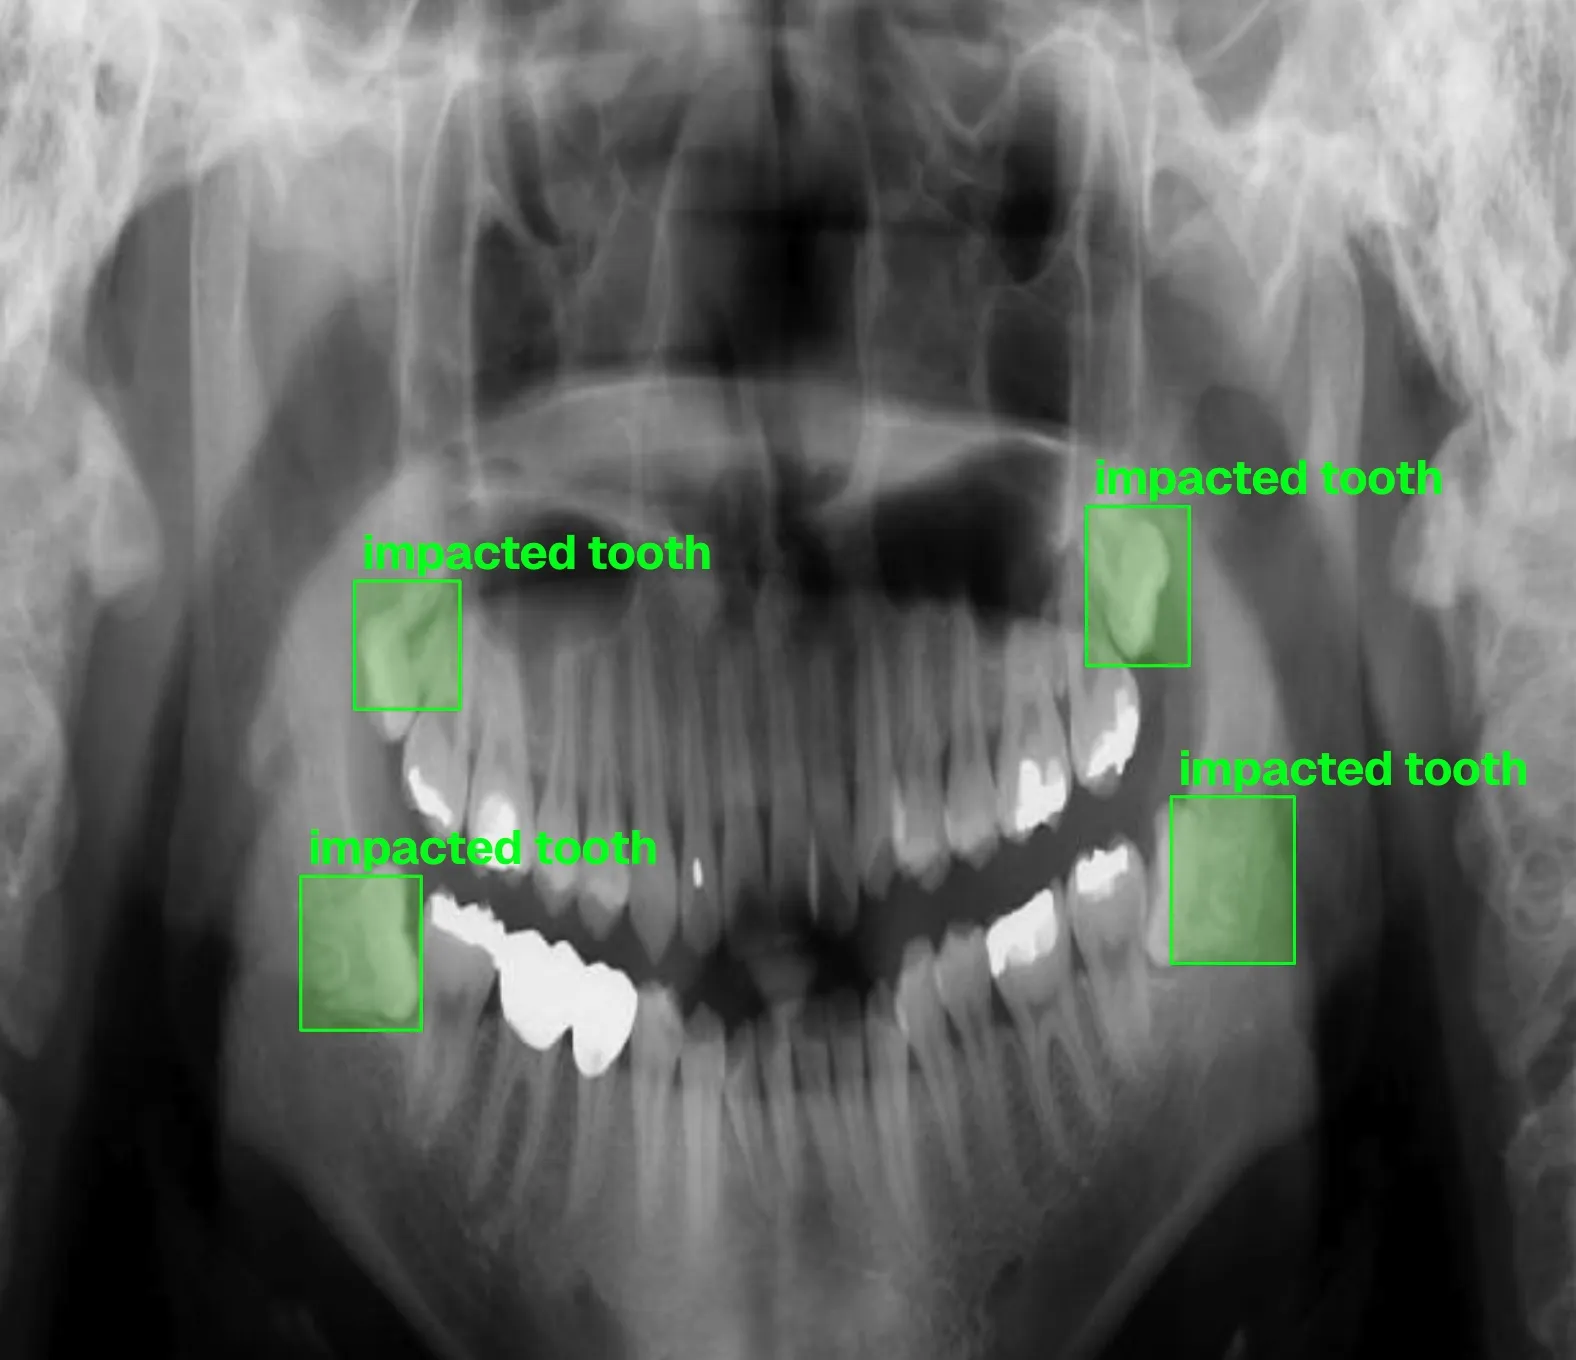

- Advanced oral surgery techniques

- •Assisted in complex oral surgeries